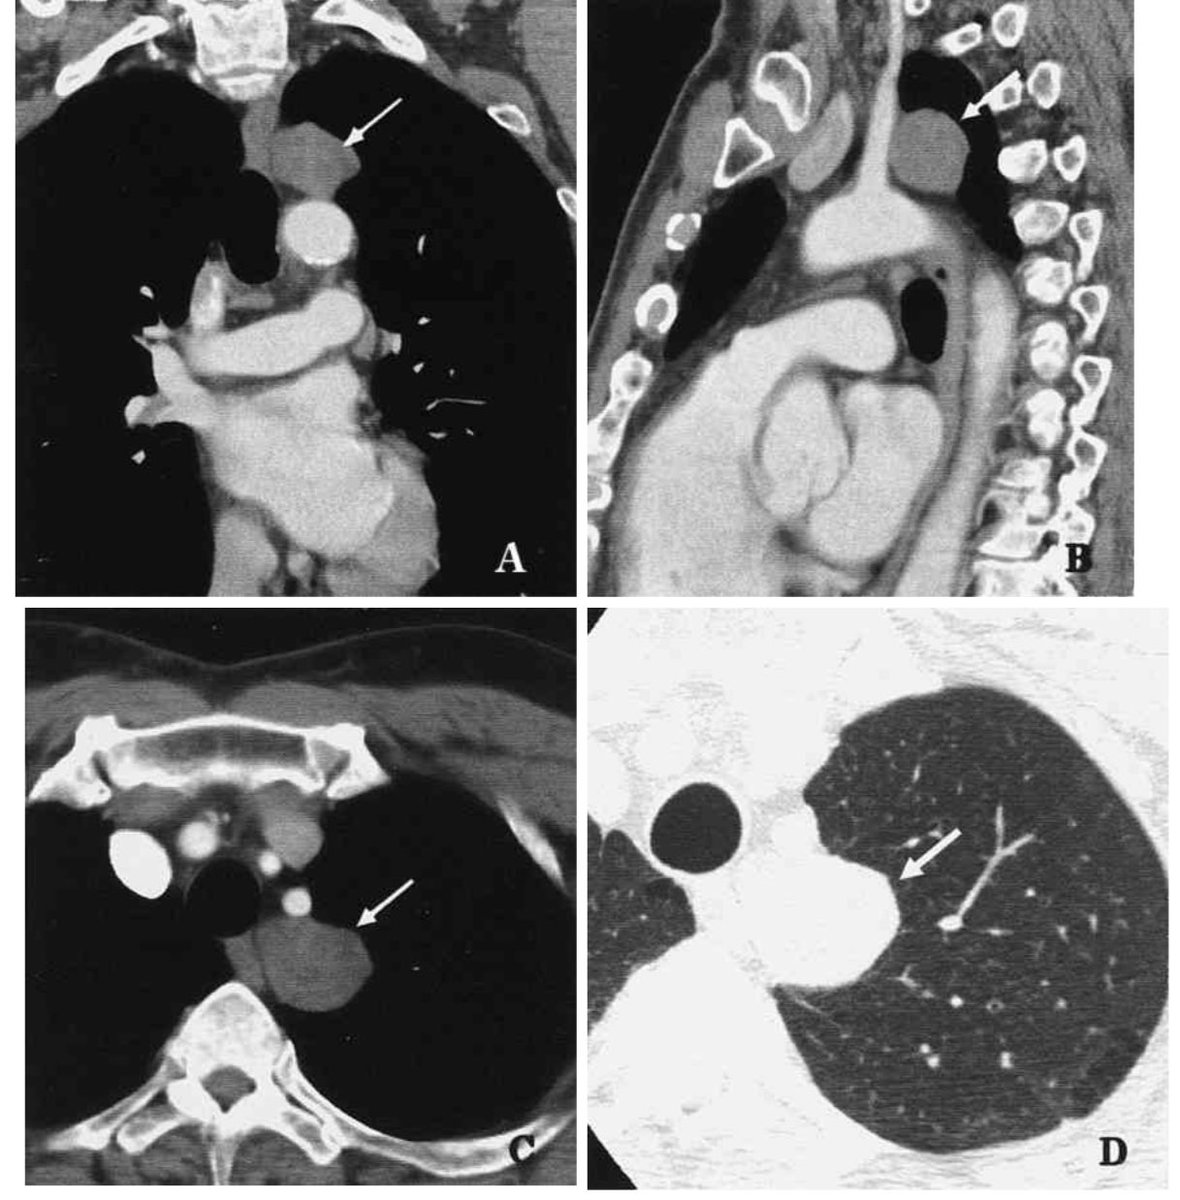

肺の単発性結節の68%、 肺の良性腫瘍の77% を占める。 40〜50歳代に好発し、男女比は23:1。小児には稀。 通常は無症状だが、気管支内腫瘍による閉塞性肺炎が原因となって、咳嗽、軽度の胸痛、発熱を来すことがある。まれに喀血あり。 過誤腫の画像診断 肺硬化性血管腫の画像所見 境界明瞭な15cm大 の結節、腫瘤影を呈する。 通常は 充実性 。内部に嚢胞を来すこともある。 石灰化は10%で認められ、中心性に認められる事が多い。特集肺癌画像診断05年一肺結節の良悪性鑑別の進歩 図1 肺過誤腫 70歳代女性 a hu pu a HRCT肺野条件。 右下葉肺底部に15mm大、辺縁整で一部わずかに分葉状の形態を呈する結節あり。 b,c HRCT縦

胆管過誤腫(von Meyenburg complex)とは胆管壁組織の遺残より発生する胆道系との交通を 持たない嚢胞性病変で、剖検例では069~56%に認められ、無症候性に画像診断等で発見さ れることが多い。通常胆管過誤腫はFDGPET陽性となることはない。今回胃癌ESD後のフォ肺過誤腫のCT所見 特にepitheliallined cleftと肺動脈枝の関与について 並列タイトル (alternative) CT findings of pulmonary hamartoma with special reference to epitheliallined clefts and connection with pulmonary arteries 著者 (creator) 叶内哲 星俊子過誤腫 Wikipedia 過誤腫と病理学的に診断される機会の多い肺過誤腫を例に挙げれば,胸部X線検査や CT検査で偶然発見される孤発性のcoin lesion (銭形陰影)を示す「腫瘍様」病変である 。 切除された病変を病理組織学的に検査すると、分葉状に気管支軟骨